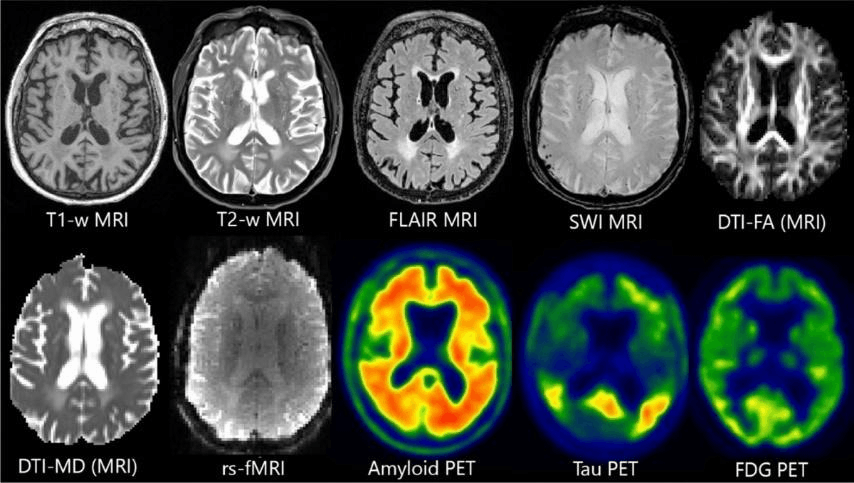

Процесс постановки диагноза любому пациенту невозможно представить без процедуры диагностики. В лучевой диагностике это исследования методами КТ (компьютерная томография), МРТ (магнитно-резонансная томография), ПЭТ (позитронно-эмиссионная томография) и так далее (рис. 1). Базовые принципы этих методов подробно разобраны в статьях «Увидеть то, что неподвластно глазу: как радиомика помогает врачам в диагностике опухолей» [1] и «12 методов в картинках: нейробиология» [2]. Необходимое диагностическое исследование выбирается в соответствии с исследуемой патологией. Например, если исследуются кости — то лучшим методом можно считать КТ, что обусловлено высоким атомным номером кальция, приводящим к значительному ослаблению рентгеновского излучения и создающему высокий контраст. Если мягкие ткани — МРТ, поскольку данный метод, основанный на явлении ядерного магнитного резонанса, позволяет визуализировать различия в времени релаксации T1 и T2 протонов воды в тканях организма. Однако пациента вне зависимости от проводимого исследования будет интересовать его результат. Болен или нет? А если болен, то насколько?

Рисунок 1. Примеры медицинских изображений: КТ, МРТ и ПЭТ-снимки мозга, демонстрирующие разные модальности визуализации. МРТ (Т1, Т2 FLAIR, SWI) оценивает структурные особенности мозга; DTI-FA MRI, DTI-MD MRI и rs-fMRI оценивают функционирование тканей и систем; ПЭТ используется для оценки метаболической активности мозга.